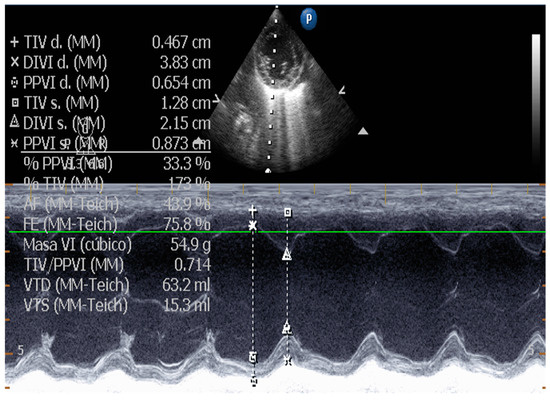

5.1. Echocardiographic Measurements on DCM

5.1.1. Measurement of Left Ventricular Volume by Simpson’s Method of Disks and Left Ventricular M-Mode